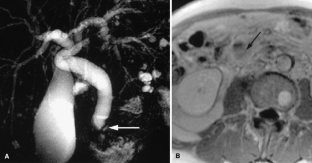

Usual and unusual causes of extrahepatic cholestasis: assessment with magnetic resonance cholangiography and fast MRI

Cholestasis may result from hepatocellular (intrahepatic) disease or biliary tract (extrahepatic) abnormalities. Etiologies causing extrahepatic cholestasis are extremely diverse and invasive procedures, such as endoscopic retrograde cholangiopancreatography (ERCP) and percutaneous transhepatic cholangiography (PTC), were previously required to establish the diagnosis. Due to refinements of magnetic resonance imaging (MRI) techniques, the patient with extrahepatic cholestasis currently can be evaluated noninvasively, and the information revealed frequently exceeds the findings obtained by ERCP and PTC. In this essay, we illustrate the classic MR cholangiographic (MRC) and MRI features of a variety of disorders causing extrahepatic cholestasis, including non-neoplastic disorders of the biliary tract (congenital abnormalities, infectious processes, iatrogenic disorders, and postsurgical complications) and neoplastic conditions (e.g., tumors of the pancreas, biliary tree, liver, ampulla, and regional lymph nodes). In most cases, familiarity with the key MRC features in addition to information obtained via cross-sectional MR images provide sufficient information for adequate lesion characterization.